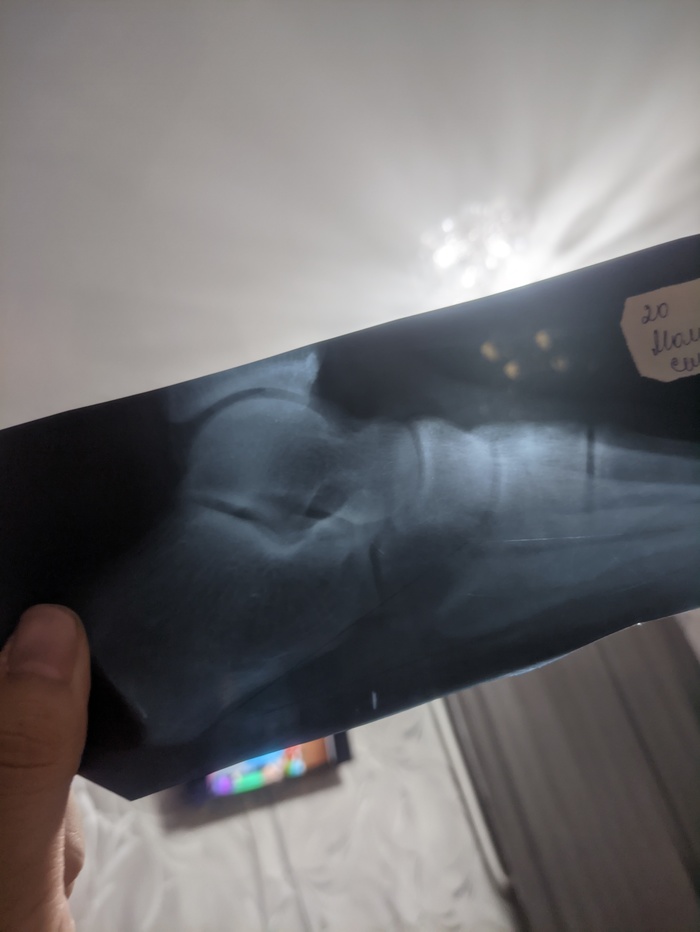

Как понять открыты ли зоны роста по снимку ?

Есть ли тут те кто разбираются в этом?

Появился интерес прибавить в росте.Ну и вот снимки 6 месячной давности попались под руку и вроде как я понял,знающие люди могут определить открыты ли зоны роста по всяким таким снимкам.Знаю что вроде по ладоням смотрят,но лень идти делать целенаправленно из за этого снимки